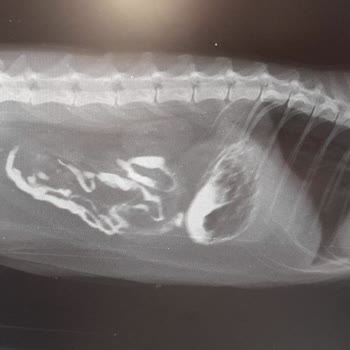

Öncelikle kesinlikle Google yorumlarına aldanıp çocuğunuzu emanet etmeyin. Kötü yorumları kaldırıyorlar, iyi yorumları da satın aldıklarını araştırınca anlarsınız. Benim kedimi yabancı madde çıkartacağız ameliyat edeceğiz diye alıp karnını kesip geri dikerek, ameliyat etmeyip, yabancı maddeyi almayı...